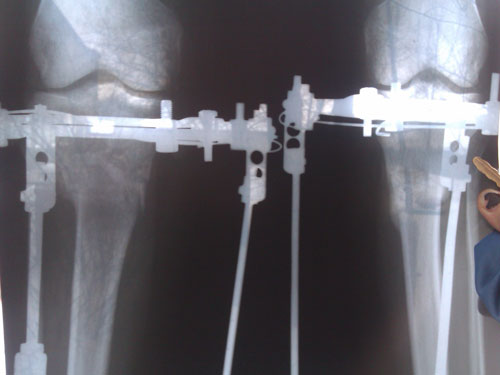

рентген.

В конце февраля ждём на снятие аппаратов!

Рентген перед снятием аппаратов.

Здравствуйте, loginza499! По рентгену, всё отлично, сращение железное. Разрешено всё без ограничений! Обувайте каблучки, нагрузка по возрастающей.